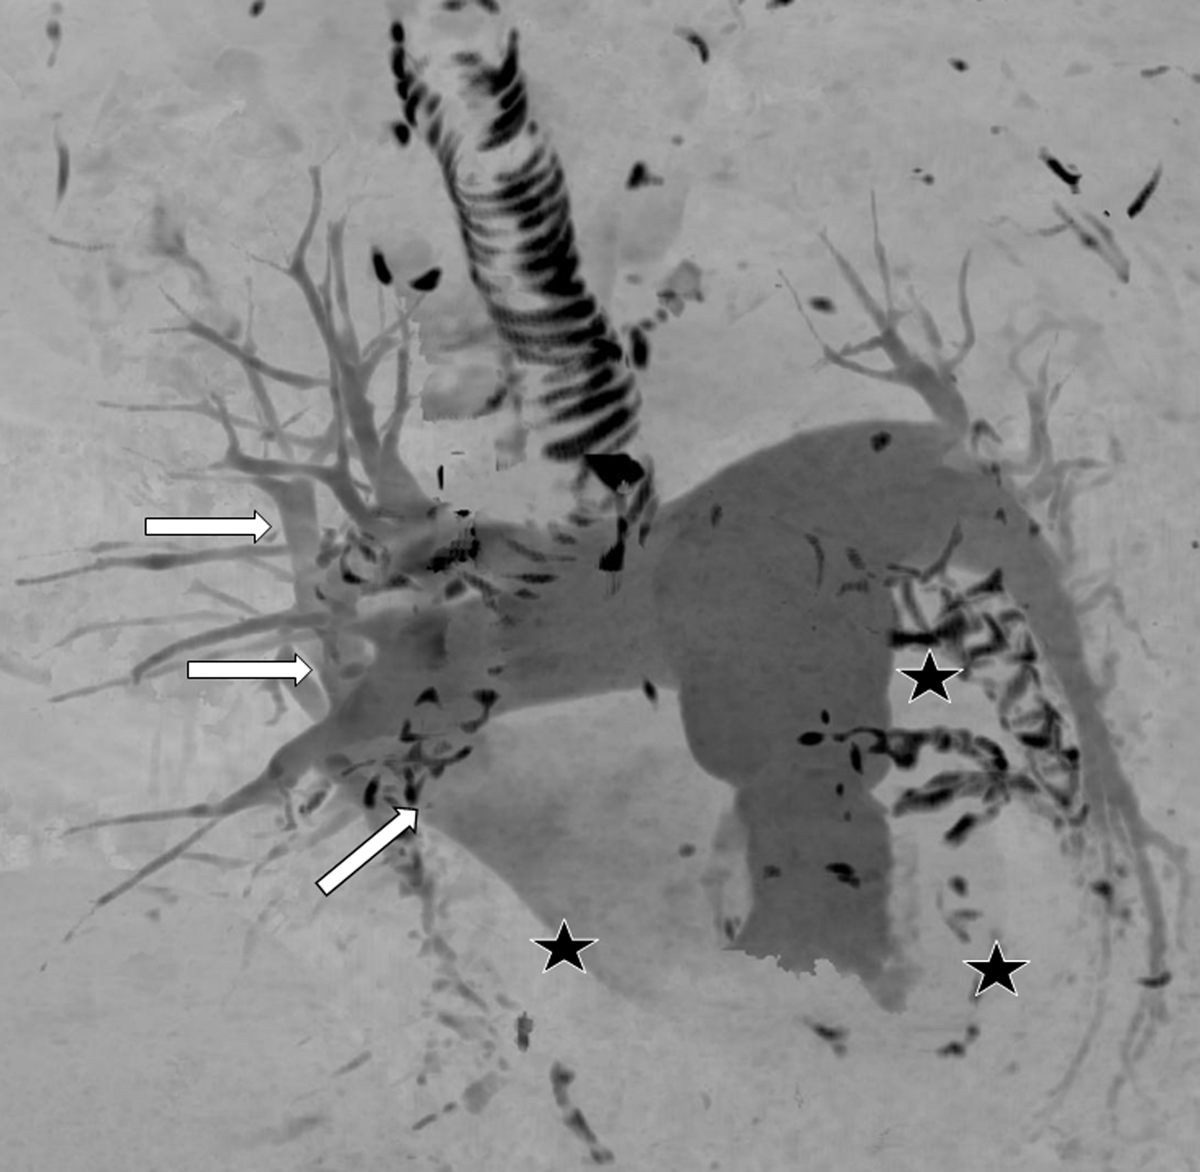

Figure 4

3D maximum intensity projection of all the pulmonary vessels in antero-posterior orientation. The PAs and the right superior pulmonary vein are opacified (arrows). Right lower, left upper, and left lower pulmonary veins are not opacified (stars). The calcified bronchial cartilage and coronary calcifications appear black.